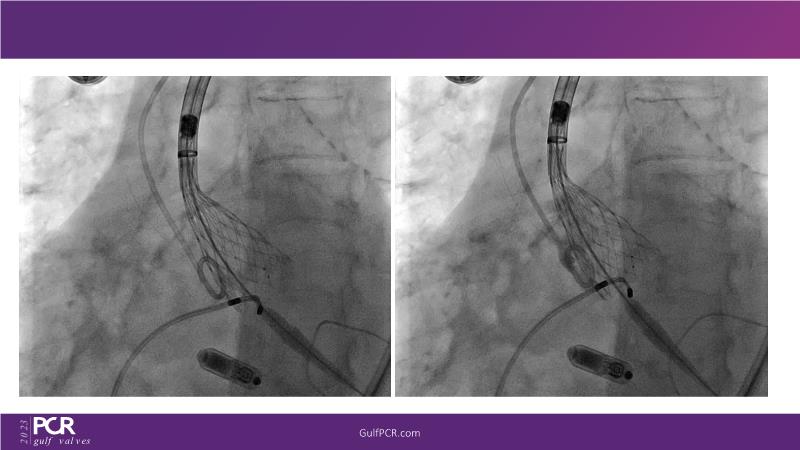

The primary focus of this GulfPCR-GIM 2023 session revolves around pre-procedural planning considerations, valve selection, and managing complex anatomies using both traditional self-expanding valves and the Evolut FX system. Additionally, the session aims to explore the work-up protocol for patients grappling with severe AS and advanced CKD, elucidate the algorithm for selecting the appropriate TAVR platform, discuss strategies to reduce contrast utilization, and highlight the distinctive advantages offered by the Evolut FX system.

• To learn more about optimization of valve deployment